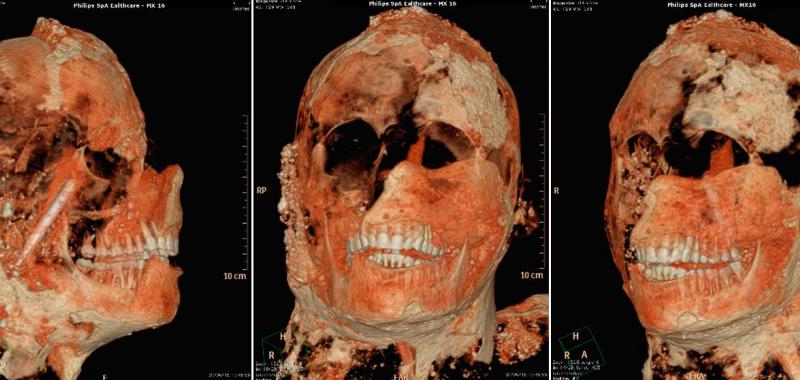

Entre las conclusiones de la investigación figura la evidencia de que tenían dientes en buen estado gracias a una buena alimentación basada en pocos azúcares, así como que se servían de la dentadura para romper y cortar alimentos y útiles relacionados con las actividades cotidianas o artesanales.

“Los dientes puden aportar información sobre los hábitos de vida de una persona, además de sobre sus ocupaciones”, cuentan los responsables de la investigación, que añaden que también averiguar si era flautista o fumador de pipa, por ejemplo, así como su origen geográfico y sus condiciones socioeconómicas”.